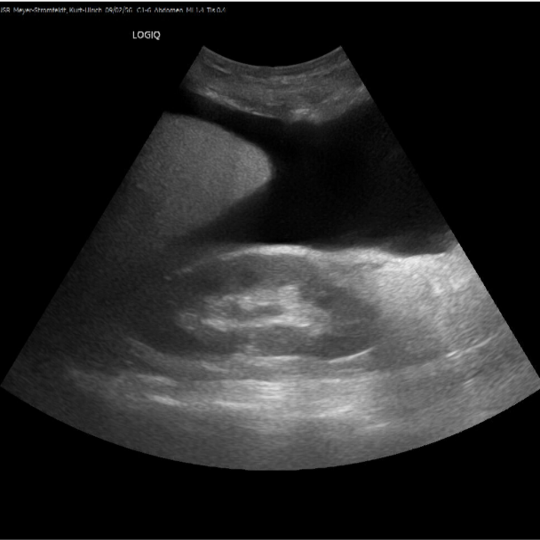

Ultraschall hat im Vergleich zu anderen bildgebenden Verfahren relativ geringe technische Anforderungen. Daher kann er für die klinische Beurteilung dort eingesetzt werden, wo der Patient oder die Patientin behandelt wird. Damit entfallen hohe Kosten und logistische Hürden, wodurch auch der finanziell benachteiligten Landbevölkerung kann eine professionelle Diagnostik angeboten werden. Point-Of-Care-Ultraschall (POCUS) wird durch das behandelnde medizinische Personal zur Beantwortung einer spezifischen klinischen Frage eingesetzt, um die Patientenversorgung und -betreuung zu unterstützen. POCUS ist relativ leicht zu erlernen und kann nach standardisierten Protokollen durchgeführt werden, wobei die Befunde leicht zu erkennen sind. Neben der Bestätigung einer akut behandelbaren Diagnose ist damit auch eine niedrigschwellige und kostengünstige Ersteinschätzung des Patienten oder der Patientin möglich.

POCUS kann bei Infektionskrankheiten wie Lungenentzündung, Tuberkulose oder Schistosomiasis, aber auch bei nicht übertragbaren Krankheiten wie Krebs und Leberzirrhose oder bei Notfällen wie Herzversagen oder Trauma eingesetzt werden. Der Einsatz von POCUS kann die Differentialdiagnose schnell eingrenzen, die Zeit bis zur endgültigen Behandlung verkürzen, die Ausfall- und Komplikationsraten bei Behandlungen verringern und die Patientenzufriedenheit verbessern. POCUS ist daher eine wichtige Innovation und dient der Optimierung der medizinischen Versorgung für die finanziell benachteiligte Bevölkerung.